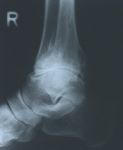

Arthrose ist eine Gelenkerkrankung bei der Gelenkknorpel und die Gelenkschmierung nicht mehr

oder nur noch zum Teil vorhanden sind. Dieses bewirkt das die Gelenkflächen aufeinander reiben

und sich daraus Schmerzen und Entzündungen ergeben. Diese Schmerzen sind von unauffällig bis

zu sehr stark je nach Patient vorhanden. Die daraus resultierende Schonhaltung ist eine Fehlhaltung

die wiederum andere Schmerzen bedingt. Es gibt verschiedene Arten der Arthrosen: